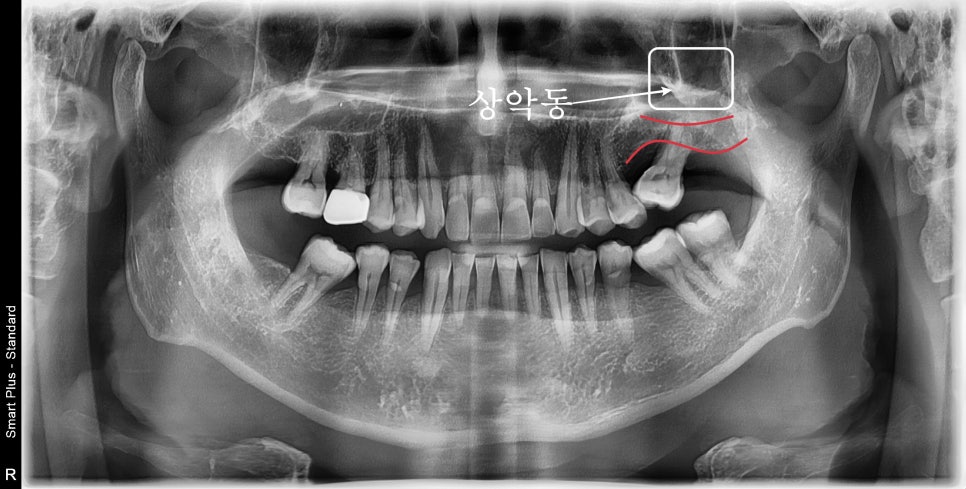

오래전에 이가 빠져서 치료를 못 받았습니다

오른쪽 위를 제외한 3공간의 어금니가 하나씩 상실되어 있었습니다.

환자분께서 과거에 치과를 올 수가 없었는데

치아가 안 좋아 발치한 상태에서 지내셨다고 하셨습니다.

특히 표시된 부분의 치아는 많이 기울어져있으며

치조골의 흡수가 심하게 일어나 종종 붓고 관리가 어려운 상황이었습니다.

사진에 표시된 바와 같이

붉은색으로 표시된 부분은 남아있는 치조골의 양이고

그 상부의 흰색 부위는 부비동이라고 알고 있는 상악동 공간입니다

그곳은 아무것도 없는 텅 빈 곳이기 때문에

원하는 임플란트를 식립하기 위해서는 상악동이라는 공간을 이용해야 합니다.